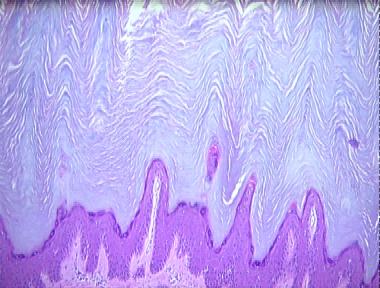

acrokeratosis verruciformis of Hopf

Histologic Features